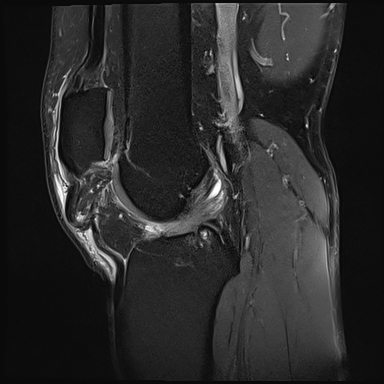

A l’examen clinique, le genou est légèrement tuméfié. La rotule semble ascensionnée et un creux est palpé sur le trajet du tendon rotulien. L’extension active est impossible. Sur les radiographies standards face et profil du genou, la rotule est ascensionnée.

L’ultrason ou l’IRM peut confirmer le diagnostic de lésion du tendon rotulien et de différencier une rupture partielle d’une rupture complète. Le traitement est chirurgical.